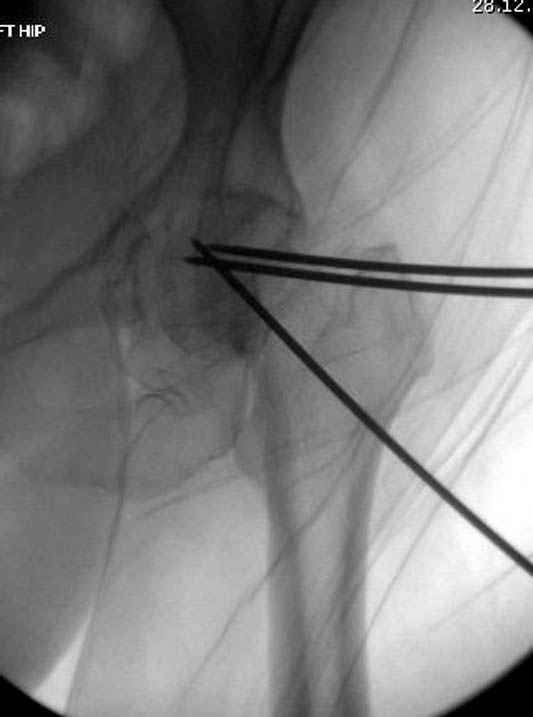

Долгое ожидание повышает риск АВН головки,

рекомендуется ургентная фиксация шейки в первые сутки, а в дальнейшем таз.

В данный момент скелетное вытяжение поучается через перелом шейки, а фиксированный перелом шейки будет участвовать в процессе вытяжения через каннюлированные шурупы.

Перелом шейки смогли зафиксировать через пару дней, ацетабулум до сих пор не оперирован, на вытяжении.